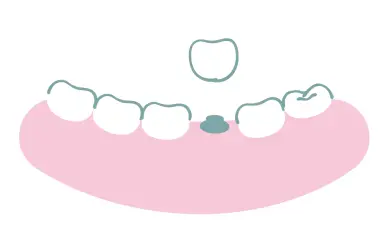

インプラント骨造成

Before

After